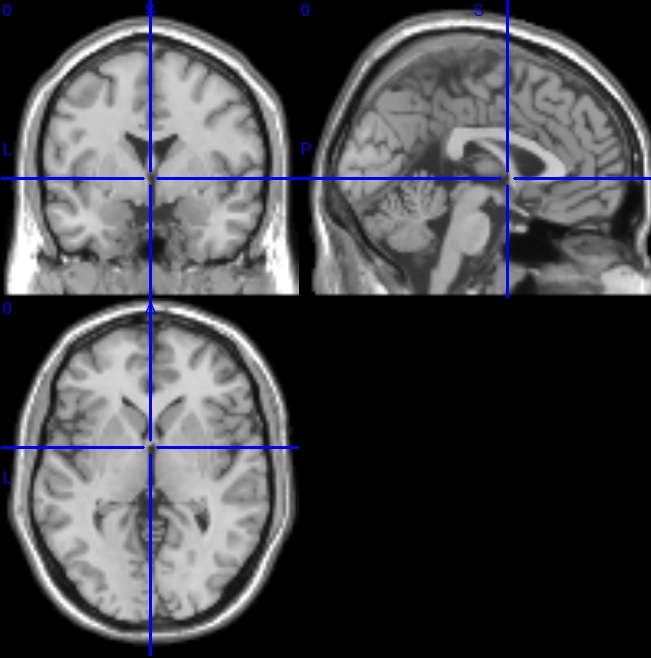

内部限定(プレビュー) Internal limited 本ページの記事は東北大学応用認知神経科学センター内部での情報共有を目的としており外部からの閲覧を想定していません。センターは内容について外部からのご質問にはお答えできず、正確性に関して責任を負いません。 fMRIデータの前処理 fMRI解析マニュアル SPMを用いたMRI解析を始める前に、以下の準備が必要です。 前処理を行う前の確認 原点合わせ Realign Slice timing correction Coregistration Segmentation Normalisation Smoothing ※必ずしもこの手法をこの順番で行うとは限りません 質問、ご指摘、ご意見がありましたら、フォームより入力ください。 添付ファイル 一覧へ戻る 前の記事 一覧へ戻る 次の記事